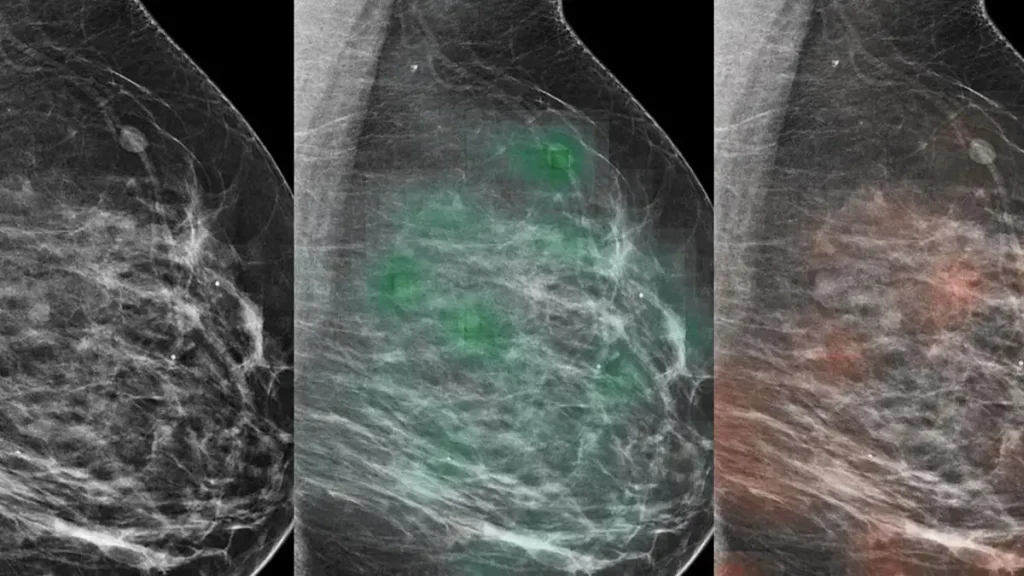

A look at how Linda Moy, MD, professor of radiology at NYU Langone Health is working with colleagues at NYU Center for Data Science on AI approaches to improve breast cancer screening.

An AI tool trained on roughly a million screening mammography images identified breast cancer with approximately 90 percent accuracy when combined with analysis by radiologists, a new study finds.